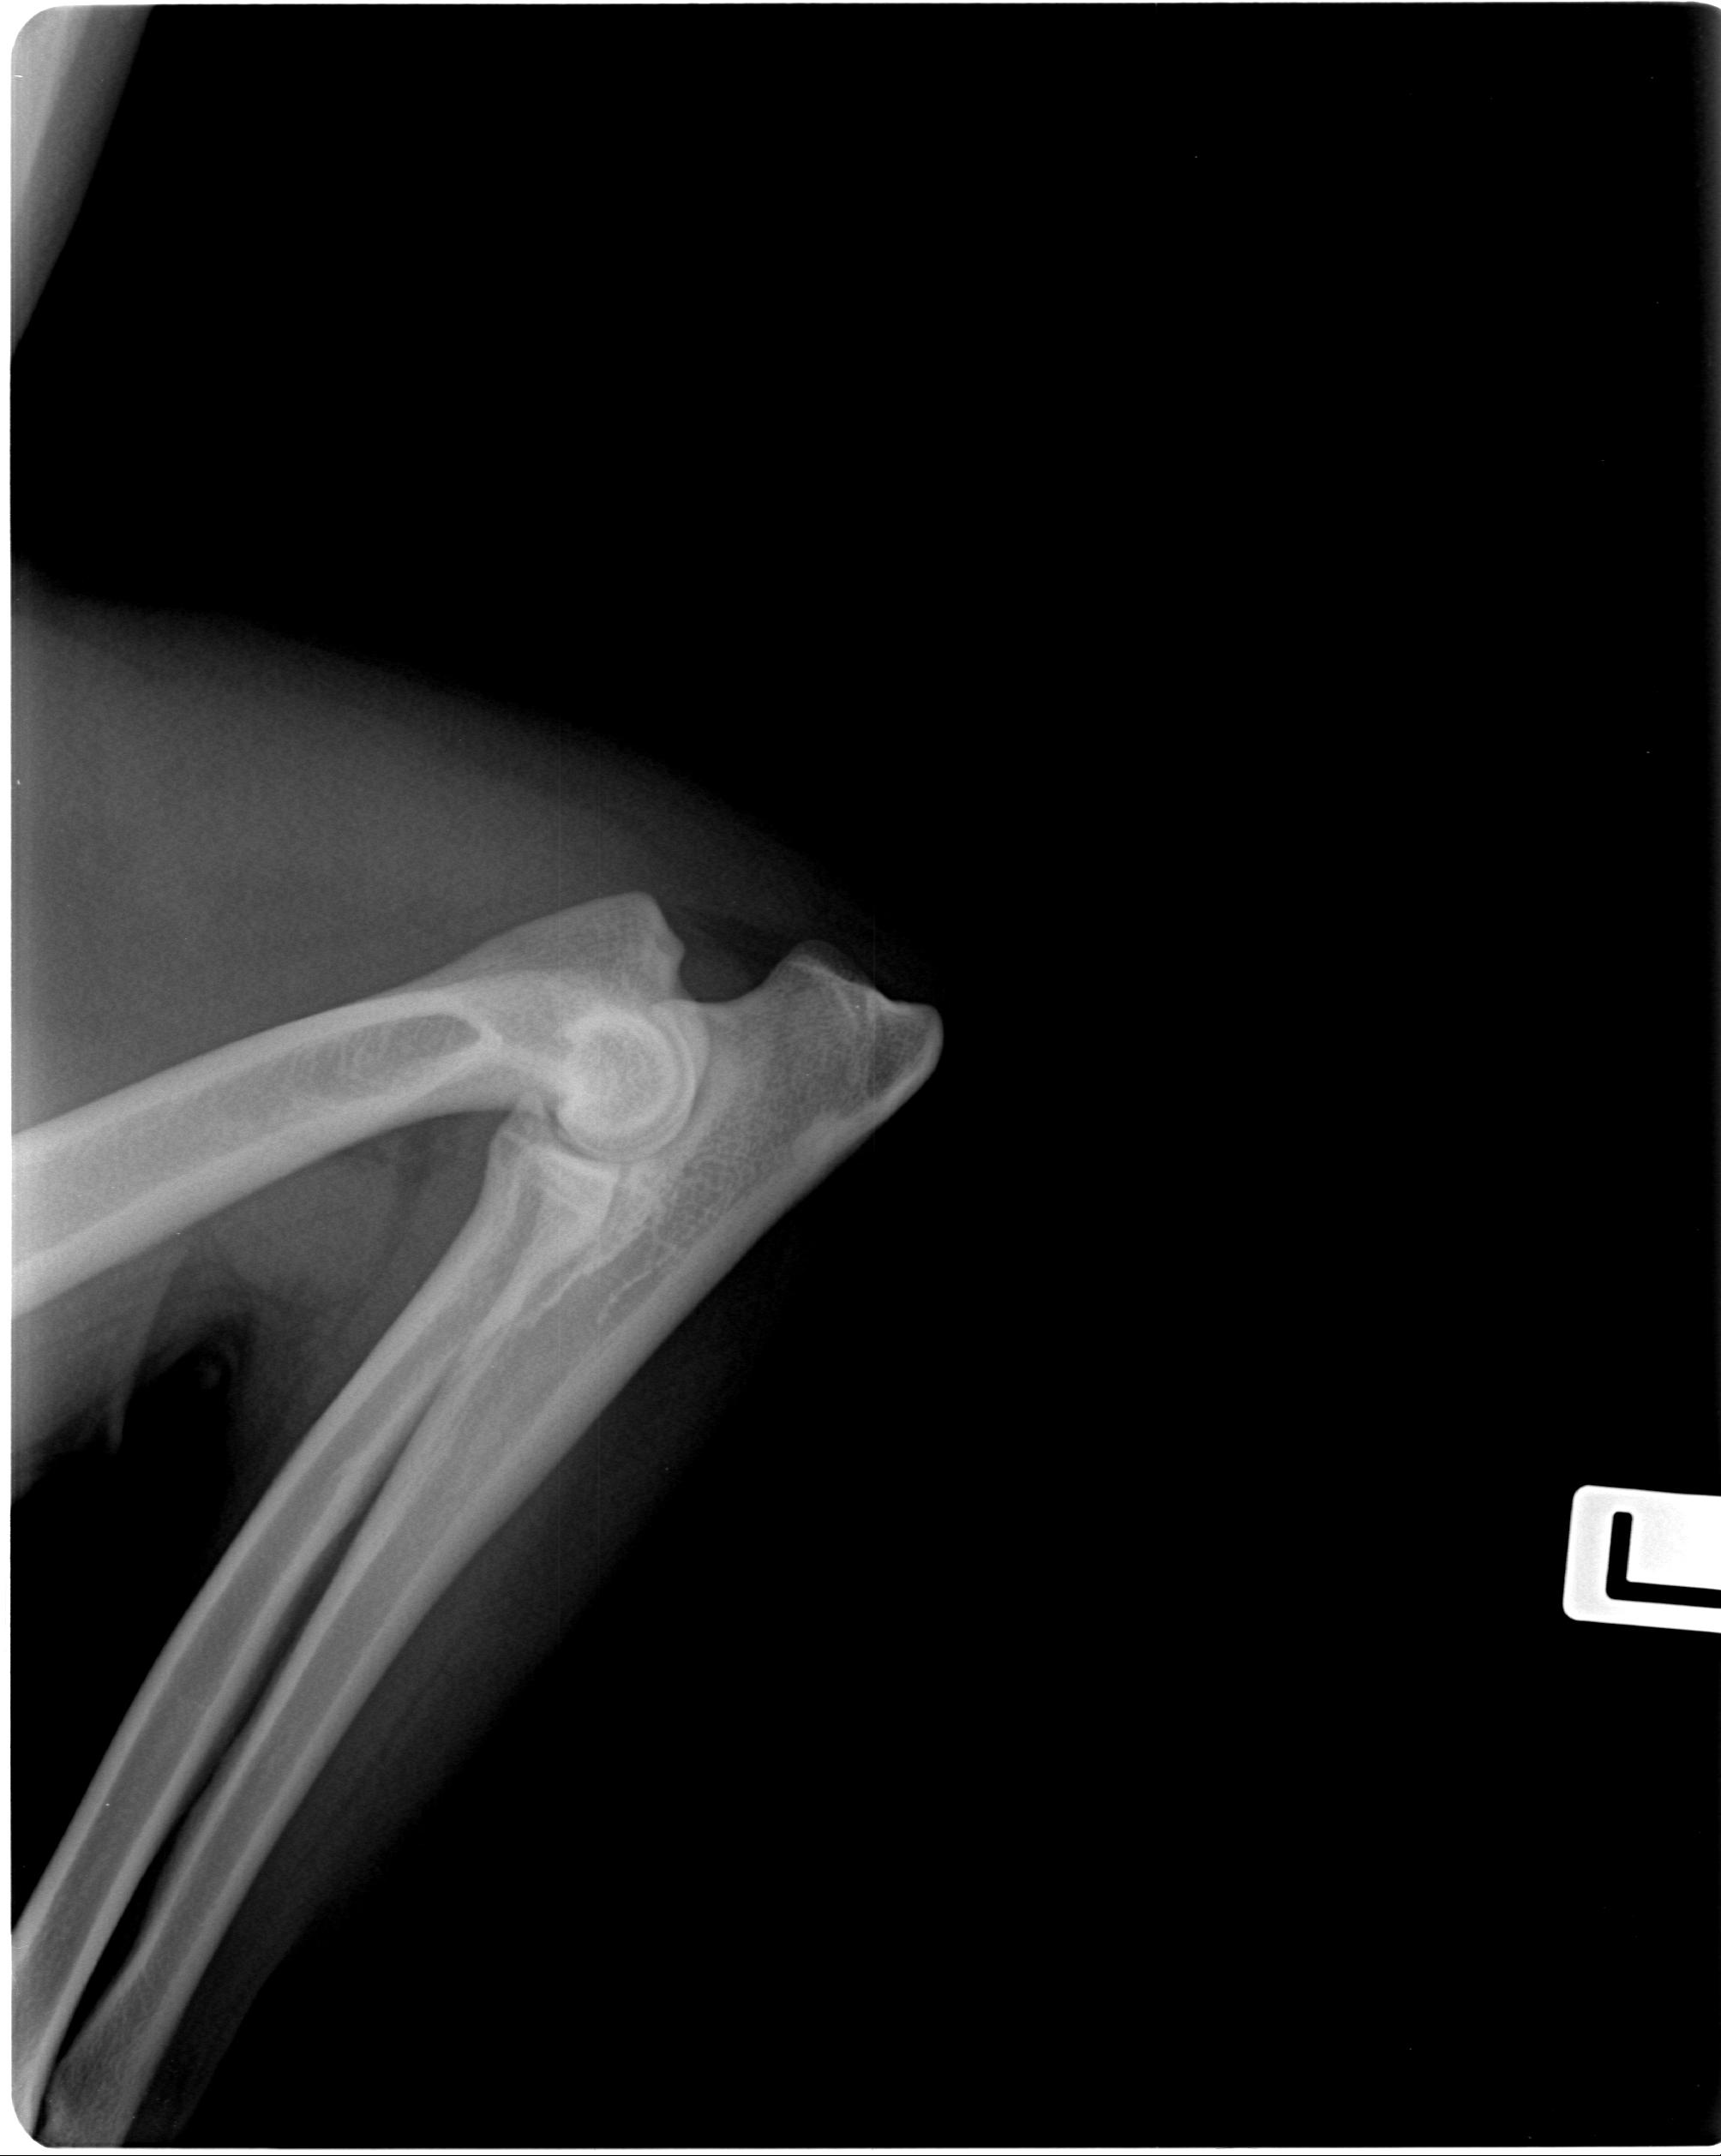

Ellenbogendysplasie (ED)

0/0

Röntgenaufnahmen

Ausgewählte Röntgenaufnahmen geben einen ergänzenden Einblick in die orthopädischen Untersuchungen dieses Zuchthundes. Die offiziellen Ergebnisse zu HD und ED finden Sie in der Übersicht oben. Weitere Nachweise stellen wir bei ernsthaftem Interesse gern zur Verfügung.